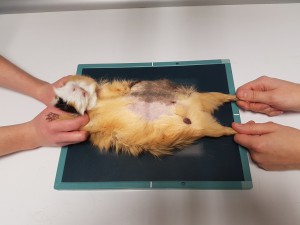

- Césarienne

Portée de jack russel mis au monde par césarienne un samedi matin